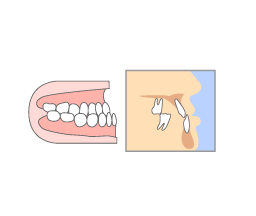

「歯がしみる」「歯が痛い」

そんなむし歯の症状が出てもすぐに受診せず、痛みに耐えられないような状況になってから歯科医院に訪れる方が多くいらっしゃいます。

しかし、むし歯は痛みを感じる頃にはすでに進行していることがほとんどで、ぎりぎりまで痛みを我慢していた場合、治療の時間や費用が多くかかってしまいます。

また、重度まで進行してしまっているむし歯は、神経を抜く必要があったり、場合によっては抜歯が必要になることもあります。

「むし歯かな?」と感じたら、お早めの受診を心がけましょう。

むし歯の進行状況を正確に判断し、丁寧に治療のご説明をしてから治療に入ります。

進行状況に合わせた治療を行うことで、歯の削りすぎを防ぎ、患者様の歯を少しでも多く残せるように心がけています。